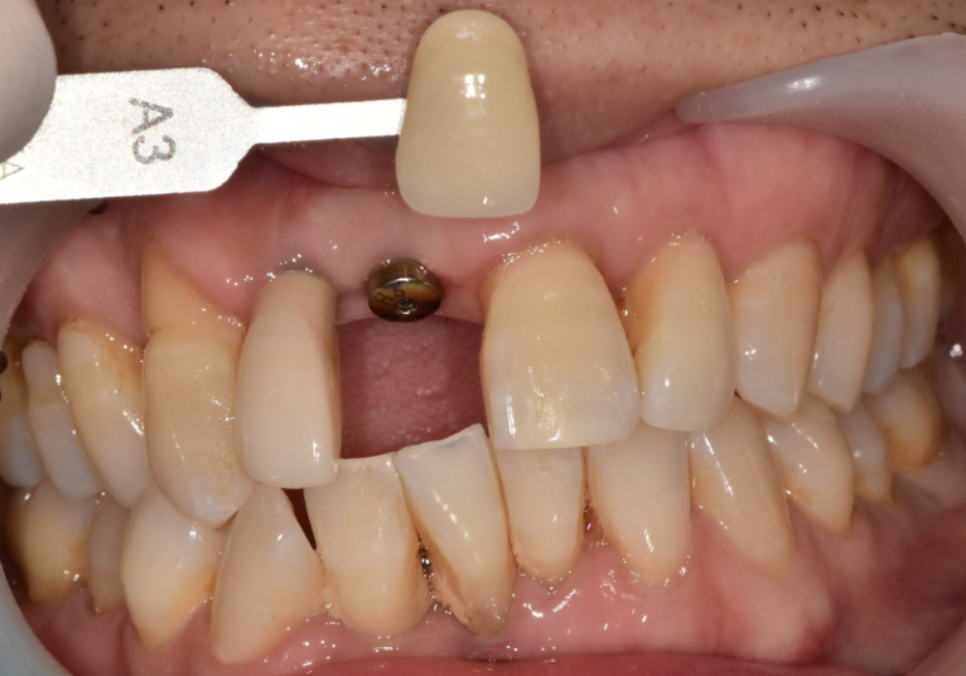

색상을 아주 조금 더 밝게 조절하거나

모양을 더 자연스럽게 만드는 과정이

실시간으로 이루어지죠.

특히 앞니 크라운이나 라미네이트처럼

미세한 차이가 중요한 심미 치료에서는

이런 소통이 결과의 한 끗 차이를 만들어낸답니다.

기존에 치료했던 오른쪽 앞니(#12)와

새로 임플란트를 심은 중앙 앞니(#11)가

자연스럽게 조화를 이루도록

보철을 제작해드렸는데요~

막상 보철물을 끼워보니 환자분께서

치아 길이가 약간 짧아 보이는 것 같다고

말씀하셨어요.

260312

사실 치아 길이는 0.5mm만 차이가 나도

사람의 인상을 좌우할 만큼 예민한 부분인 만큼,

치아의 모양이나 길이는

옆 치아의 영향을 많이 받는 상대적인 영역이에요.

이전에 임플란트를 했던

오른쪽 앞니가 살짝 길다 보니,

중앙 앞니가 상대적으로 짧아 보였던 것이죠.